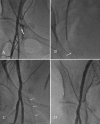

Iatrogenic common femoral artery pseudoaneurysm is a well-described vascular access complication. Several methods have been proposed to treat these pseudoaneurysms. In this report, we present three cases of successful pseudoaneurysm closure using a novel method of retrograde pseudoaneurysm access and thrombosis with Angio-Seal (St Jude Medical, St Paul, MN) closure device. This technique appears safe, effective, and reduces patient discomfort.